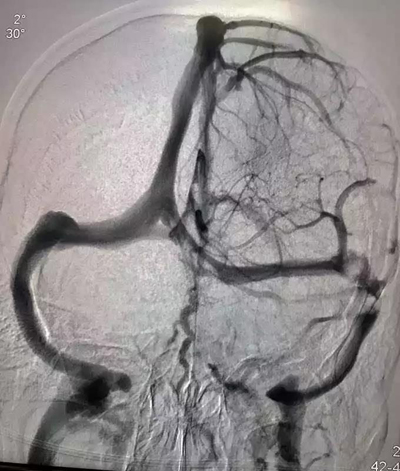

2018年12月4日,27岁的患者赵某某因视物模糊逐渐加重到医院检查治疗。经过眼底检查,发现患者双眼视乳头严重水肿。到底是什么原因引起患者视乳头出现水肿?腰穿提示患者颅内压增高,严重的颅内压增高可导致视乳头水肿、甚至脑疝,危及生命。头颅MRV、脑血管造影术等相关检查均提示右侧横窦血栓形成、狭窄可能,故给予抗凝、降颅压等治疗,但患者颅内压仍进行性增高,这意味着患者的视力会逐渐下降,甚至失明,患者及家属心急如焚。经医护人员认真讨论后认为,在抗凝等保守治疗效果欠佳的情况下,可进行颅内静脉窦支架植入术。但颅内静脉窦支架植入术难度高、风险大。为确保手术顺利完成,医院特邀首都医科大学附属天坛医院神经介入中心莫大鹏教授协助完成该手术。2019年1月5日下午,在全麻下为患者成功实施了颅内静脉窦支架植入术。术后造影显示患者右侧横窦狭窄消失,血流通畅,术后患者双眼憋胀感明显缓解,复查腰椎穿刺术,患者颅压降至正常,手术效果非常明显。